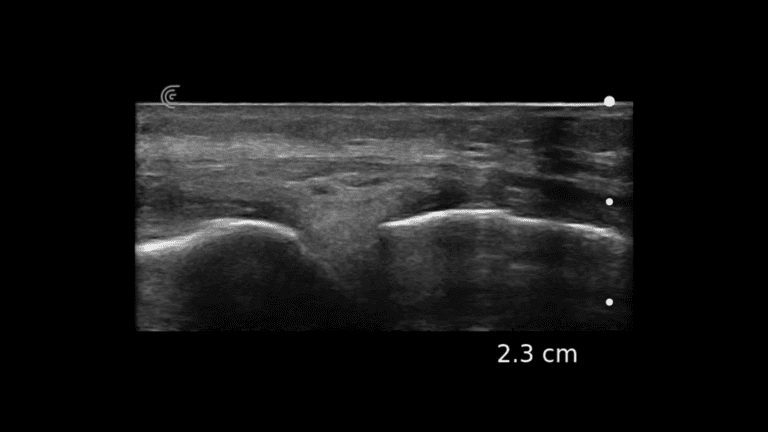

Quickly and confidently identify Achilles tendon rupture and/or tendinopathy at its insertion or mid-span or identify tears of the gastrocnemius muscle.